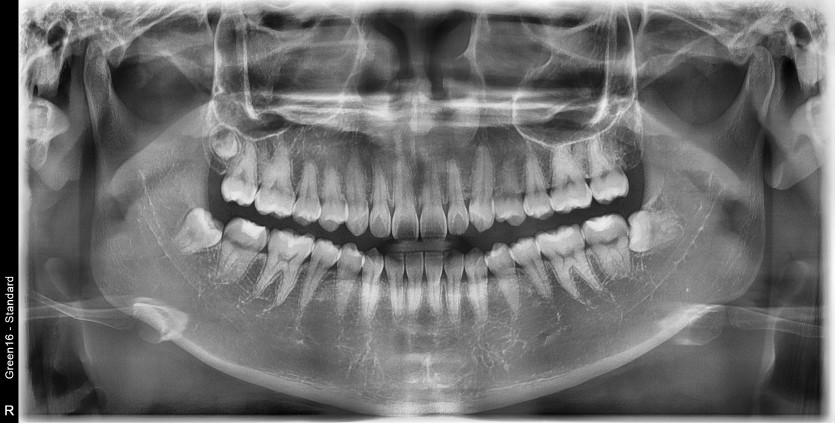

#38,48 사랑니 발치

구강 외과 전문의가 당일 발치했습니다.